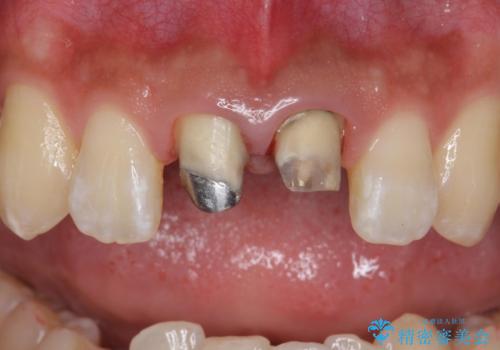

- 前歯のかぶせ物の変色を主訴に来院された患者様です。

根管治療からのやり直しはご希望されませんでした。

今回はe-maxクラウンで修復していきます。